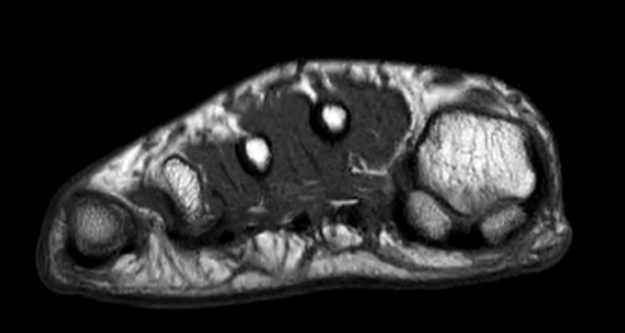

RM Avampiede

La struttura del piede, a causa dei suoi assi sempre variabili e discontinui) non consente la creazione di un protocollo standard per uno studio generale di tutto il piede. E’ quindi necessario dividere il piede in 4 zone principali: dita, metatarsi, tarso, caviglia; ciascuno con i suoi piani e protocolli specifici. STUDIO DEI METATARSI QUESTIONARIO…